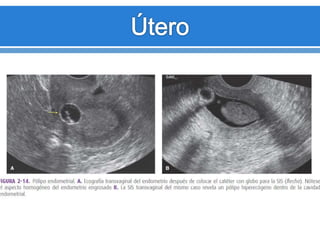

Pólipos

endometriales

Engrosamiento

endometrial

ecógeno

inespecifico

(Difusos o Focales).

Masas

ecógenICASas

focales, redondas.

ECOHISTEROGRAFIA

Pólipo ecogeno bien definido. alfombra de pequeños pólipos. Pólipo sobre su tallo

Pólipo con área quística. Pólipo pequeño pólipo pequeño

Atrofia endometrial Mujeres postmenopáusicas. Endometrio menos a 5mm. Pólipos endometriales Engrosamiento endometrial ecógeno inespecifico (Difusos o Focales). Masas ecógenICASas focales, redondas.

ECOHISTEROGRAFIA Pólipo ecogeno biendefinido. alfombra de pequeños pólipos. Pólipo sobre su tallo Pólipo con área quística. Pólipo pequeño pólipo pequeño